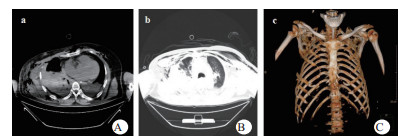

1 资料与方法患者,男,63岁,因“车祸致呼吸困难1 d”入院。既往体健。患者于2019年9月30日翻车致胸部挤压性创伤,伤后出现极度呼吸困难,送至当地医院,测血压80/50 mmHg(1 mmHg=0.133 kPa),胸部CT提示右侧血气胸,给予输血补液、去甲肾上腺素维持血压,经鼻气管插管呼吸机辅助通气,放置胸腔闭式引流管2根。因循环及氧合维持困难,10月1日转至徐州医科大学附属医院,收入EICU。入院查体:T 36.7℃,P 152次/min,R 14次/min(机械通气支持),BP 110/67 mmHg[去甲肾上腺素0.5 μg/kg·min)维持]。处于镇静状态,双侧瞳孔等大等圆,直径约2.0 mm,对光反射未引出;全身多处皮肤软组织擦挫伤,颈部及前胸、上肢广泛皮下气肿,右侧胸壁显著塌陷,反常呼吸,听诊双肺呼吸音低;心率快、心律齐、心音不遥远;腹部无异常体征;2根胸腔闭式引流管引流通畅。入院当天CT检查显示:双侧肋骨骨折伴右侧胸壁塌陷,两肺挫伤、创伤性湿肺,右肺撕裂伤,右侧液气胸,双侧胸壁广泛皮下气肿(图 1:A, B, C);未见颅内出血及腹部器官损伤。入室后0.5 h血气分析:pH 7.18,PCO2 57.5 mmHg,PO2 67.1 mmHg,Lac 4.4 mmol/L,氧合指数67.1 mmHg,APACHE Ⅱ评分27分。治疗上予镇痛镇静、保护性肺通气策略、保温、预防感染等治疗,效果不佳,连枷胸,皮下气肿范围不断扩大,氧合指数持续<100 mmHg。于10月2日气管切开后行V-V ECMO治疗(右股静脉—右颈静脉);因右侧血胸、胸引量24 h达1 000 mL,血红蛋白下降,凝血功能显著异常,存在创伤性凝血病,采取无肝素抗凝ECMO技术,提高血流速(4.6 L / min),气流速(5 L / min),FiO2 100%;给予成分输血,监测ACT及APTT。ECMO转机1h后去甲肾上腺素停用,复查血气分析PO2 105 mmHg。此后,患者氧合和血流动力学逐步改善,创伤性凝血病已纠正,于10月7日在无肝素V-V ECMO支持下行“胸骨骨折切开复位钢板内固定术+右侧3、4、5前肋肋骨骨折环抱器内固定+右侧5、6、7、8后肋肋骨骨折环抱器内固定术+两侧胸腔闭式引流术”。术中见第5肋骨前端骨折向下外移位,3、4肋骨多段骨折,胸壁前上方完全塌陷,肺脏直接外露,胸腔内布满血凝块,术中取出血凝块共约1 000 mL。术后氧分压上升至400 mmHg,术后复查床边胸片,肺部影像学较前改善(图 2 A, B),继续无肝素V-V ECMO治疗1 d后,于10月8日开始肝素抗凝,维持ACT在160 s~180 s,APTT在40 s~50 s,肝素化期间无出血并发症发生。10月11日行自主氧合试验通过,予以撤机。10月12日复查胸部CT两肺复张满意(图 3 A, B),开始间断停用呼吸机并床边康复训练。10月28日撤离呼吸机,气切处高流量吸氧。11月15日拔除气切管。11月18日康复出院,无明显并发症发生。

| 图 1 A胸部CT纵隔窗(右侧胸壁塌陷);B胸部CT肺窗(广泛皮下积气,肺挫伤);C肋骨三维重建(多根多处肋骨骨折)。 |